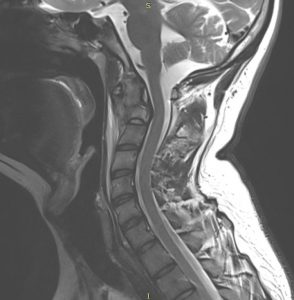

Ασθενής 20 ετών με εξεργασία στο σώμα του Α2 σπονδύλου (2ος σπόνδυλος της αυχενικής μοίρας της σπονδυλικής στήλης) με αποτελέσμα εξάρθρημα Α1-Α2 σπονδύλου και ατλαντοαξονική αστάθεια.

Αποφασίστηκε η διενέργεια ινιοαυχενικής σπονδυλοδεσίας, δηλαδή η στήριξη της κεφαλής στην αυχενική μοίρα του ασθενούς.